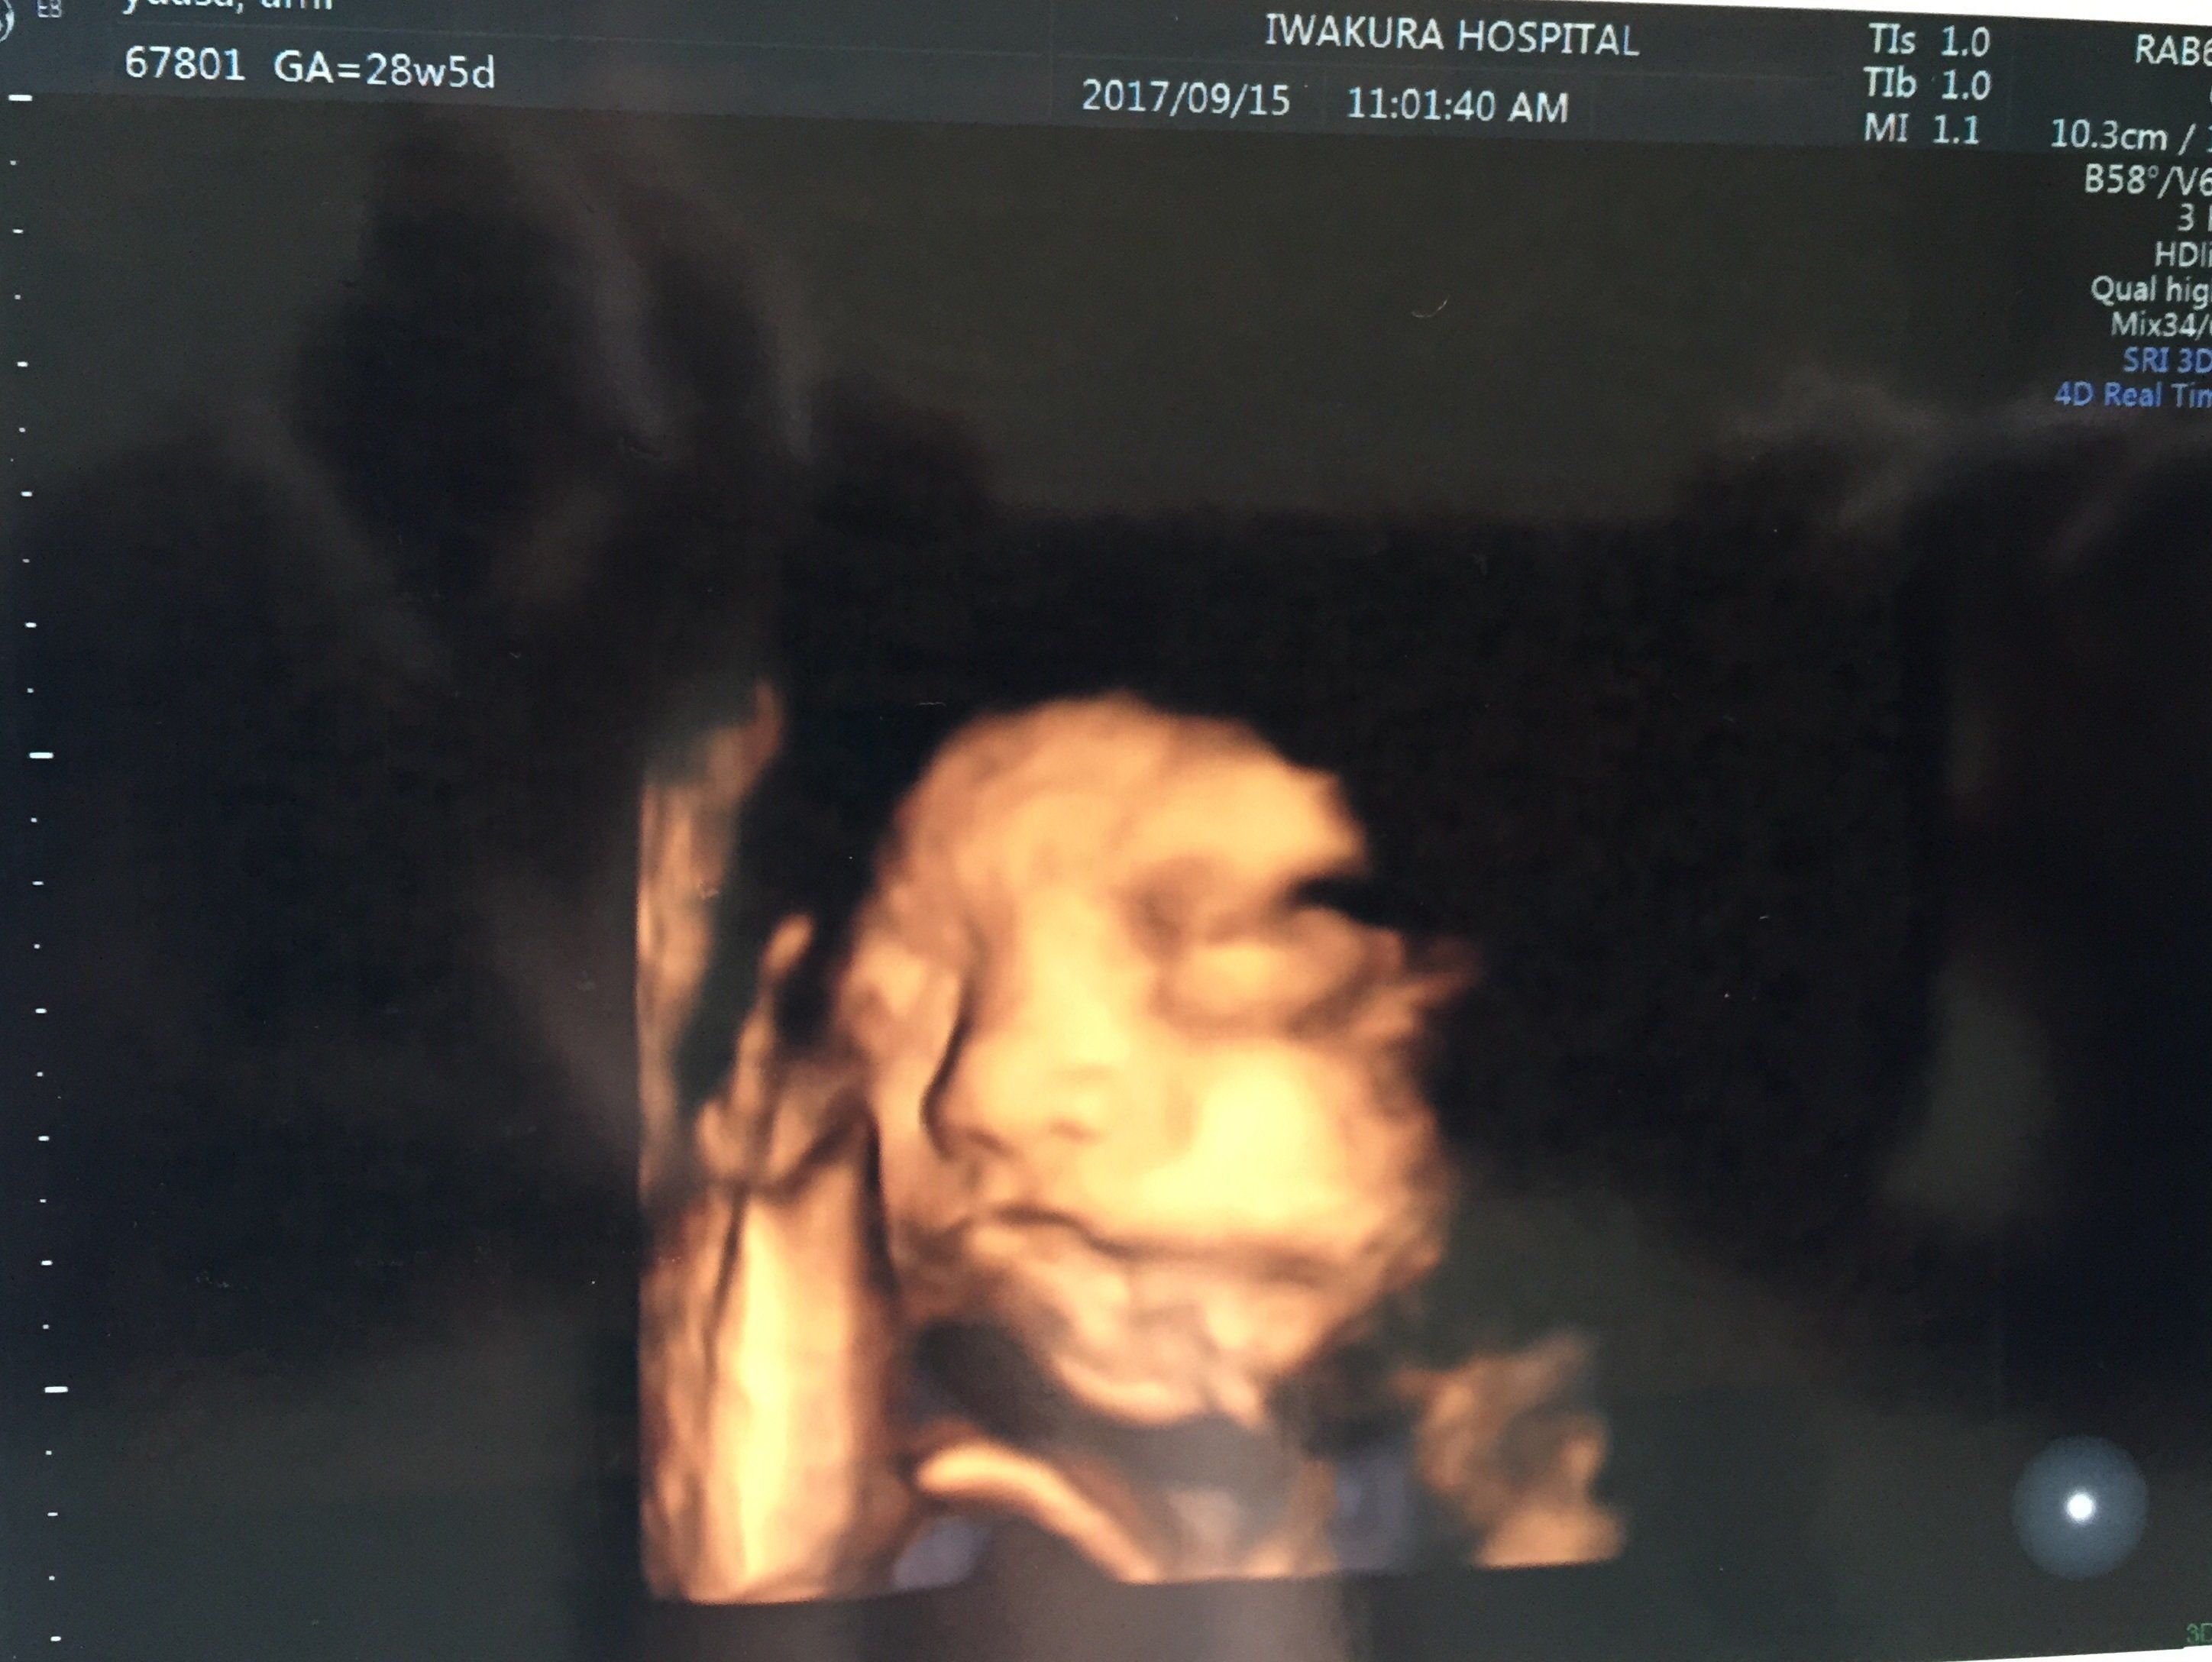

妊娠28週目のエコー写真 尿たんぱくと尿糖が出てしまい、食生活改善を心がける

前回の健診から、わずか2週間。本当ならこの日はエコーはない予定の回でした。これまでは元々、産婦人科で予定されている時のみエコーをお願いしていましたが、前回かわいいい息子のお顔を見てしまったのでもう会いたい衝動が抑えきれず、別料金を払ってお願いしてしまいました。2週間なので劇的な変化はありませんでしたが鼻が高くなり、顔のパーツがよりはっきりしてきた感じがします。なんとなくパパ似かなと想像できました。

エコー中にも赤ちゃんはよく動いており、そのためおなかの側面にお顔が近付き過ぎてエコー画像がゆがんでしまっています。今どきのエコーは画像が鮮明なだけでなく、動きもスムーズで見やすいので赤ちゃんがおなかのなかでどんな動きをしているのかが見られて不思議な感覚です。